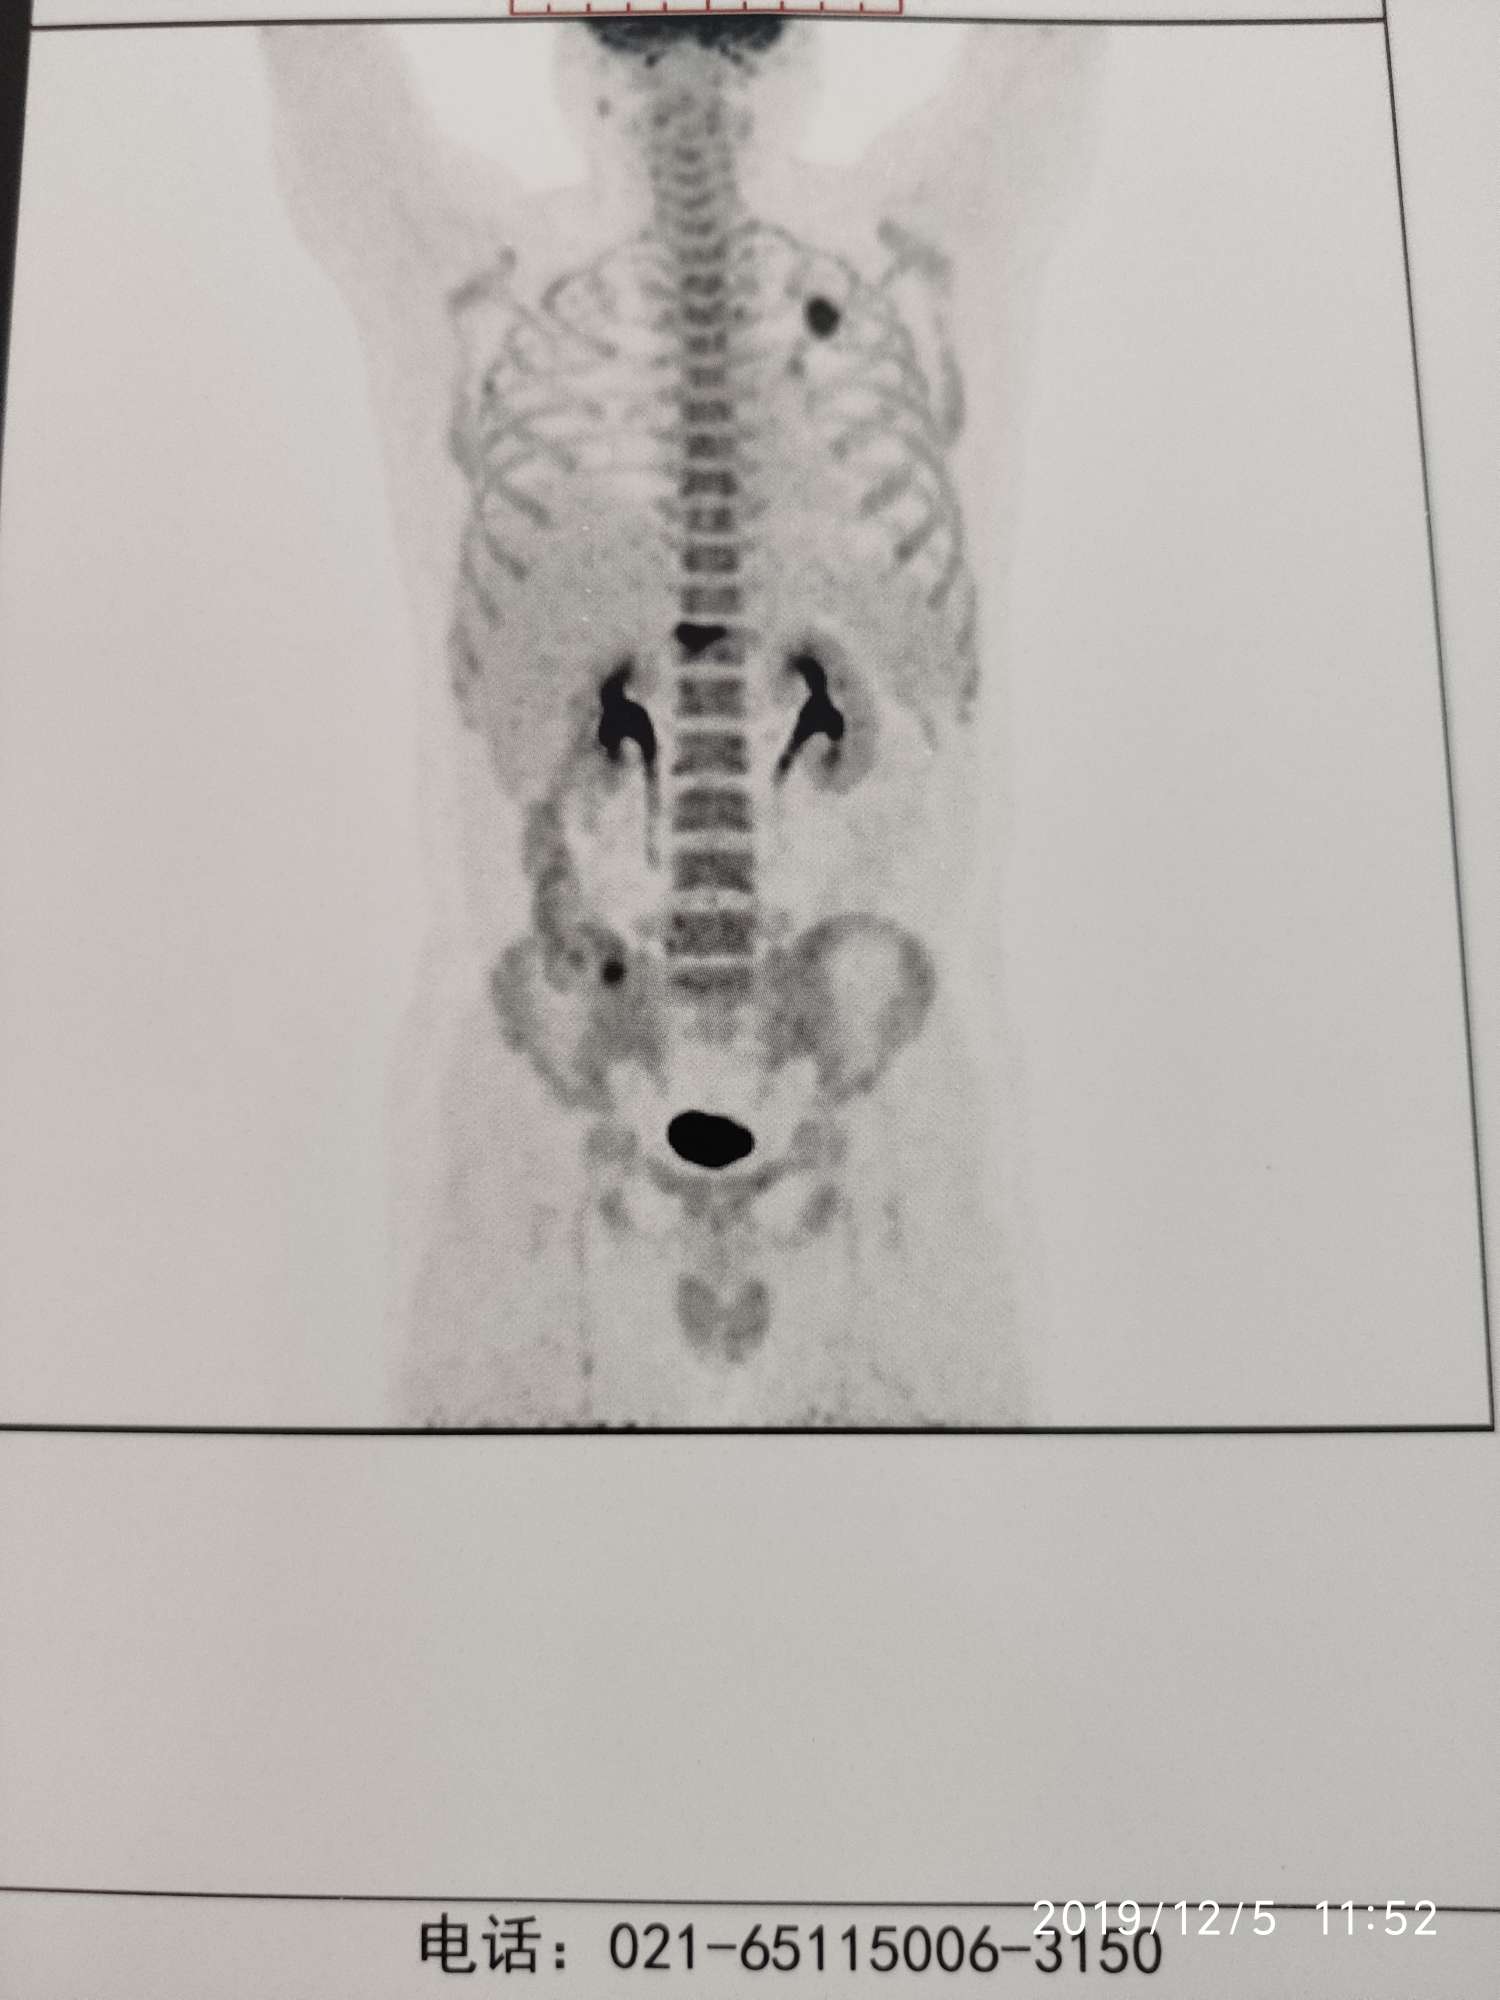

5月份检查出肺部有占位,之后马上去上海肺科做了手术(这是个失误,当时对这个病了解不多,家属强烈要求下做了),做完肺部手术后,马上转院去上海肿瘤医院进行后续的治疗。petct显示有骨转移。

上图是确证时候的PETCT